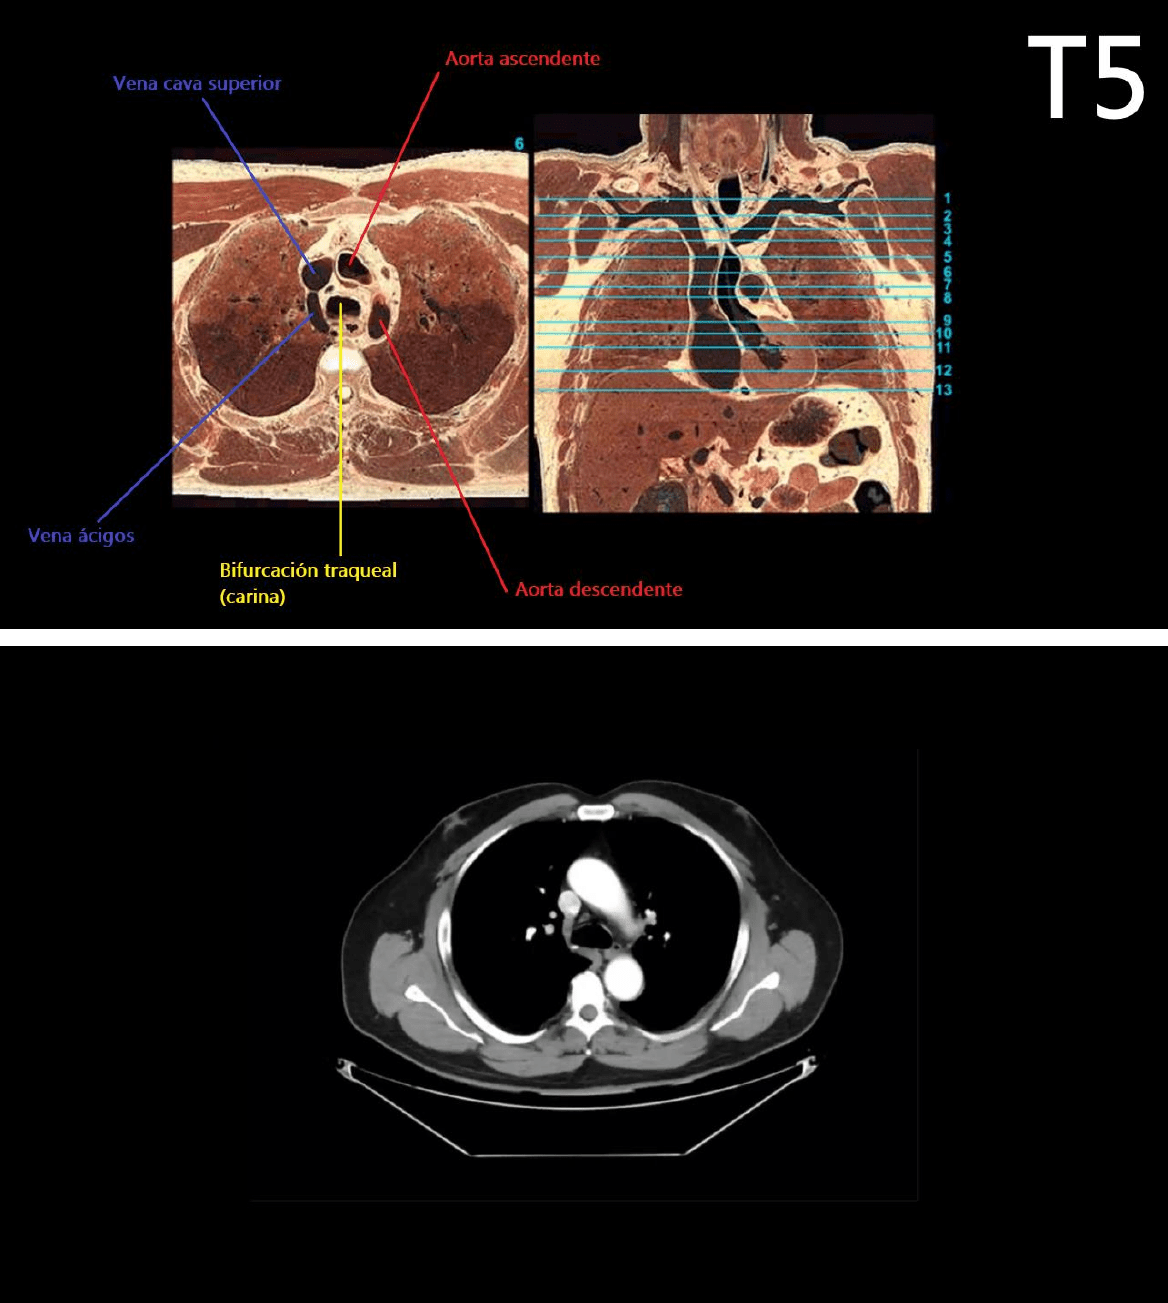

1.- ESPACIO RETROESTERNAL: Patologías donde se ve radioopaco, agrandamiento de aorta ascendente, agrandamiento

del timo, agrandamiento de glándula tiroides.